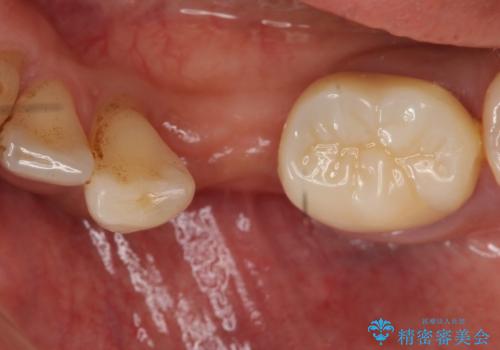

歯列矯正は御希望されなかったため左下4、5番目の歯を抜歯し、インプラントによる欠損補綴を行いました。

左下6も再根管治療後、オールセラミッククラウンによる補綴を行いました。

今回用いたオールセラミッククラウンはジルコニアフレームという白い素材の上にセラミックを盛っているため、審美性が非常に高いのが特徴です。

また、ジルコニアは人工ダイヤモンドの材料にも使われているほど高い強度を持っており、そのためオールセラミッククラウンは審美性だけでなく、奥歯やブリッジの補綴も可能とするクラウンです。